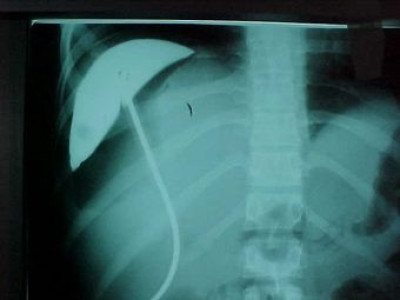

Abcseso Subfrénico

Envíado por Dr. Carlos Edgardo Escobar